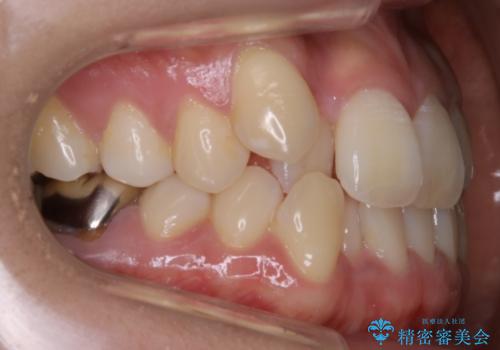

【非抜歯】インビザライン 隠れた前歯を並べる矯正治療

- 前歯のガタつき・奥に隠れてしまっている歯の矯正治療を希望されて初診来院されました。

遠心移動

非抜歯で矯正を行う場合にガタつきの改善に必要なスペースを作るために歯の遠心移動を行います。

最初の位置から奥に歯を移動させていくことで前歯のガタつきを改善したり、前歯の位置を後方に移動させることが可能となります。